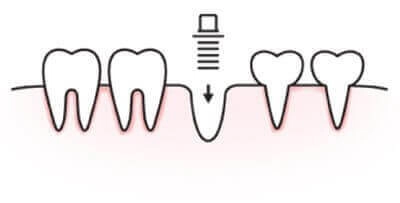

02. 置入支檯體

約3-6個月後待植體產生骨整合後,進行印模,選擇適合的支檯體。

人工植牙